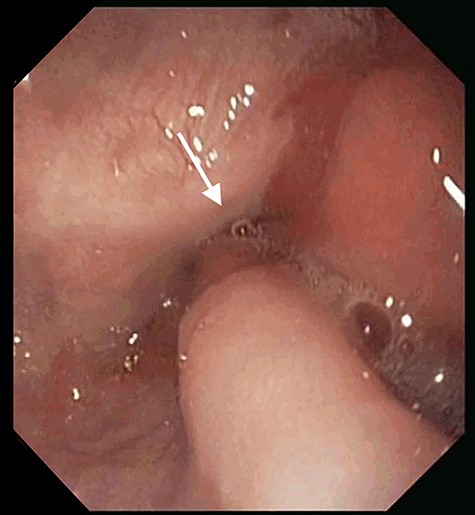

At the 24-month follow-up, an upper endoscopy confirmed integrity of the stomach pouch and GJA without any GGF (see Fig. 10). Thirty-six months after surgical treatment of the GGF, the patient remains asymptomatic and has a stable BMI.

Esophagogastroduodenoscopy image showing a normal gastric pouch with only one orifice corresponding to the gastro-jejunal anastomosis (arrow).